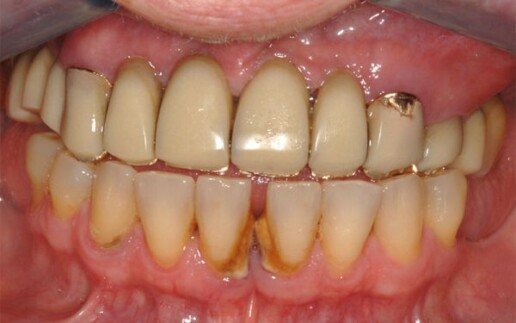

Caso 4

Riabilitazione totale superiore e inferiore su impianti. Gli esiti di una paradontite grave portano alla perdita totale dei denti. E’ necessario ricostruire sia i denti sia i tessuti molli e anche l’osso per il sostegno delle labbra.

Prima

Dopo